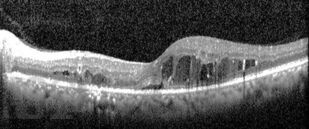

Диабетический макулярный отёк

Учебное пособие содержит информацию о диабетическом макулярном отеке. Большое внимание уделено патогенезу формирования отека в макулярной области и особенностям изменения сетчатки при сахарном диабете. Подробно рассмотрена современная классификация и основные методы диагностики диабетического макулярного отека. С современных позиций изложены основные подходы к лечению данных пациентов.